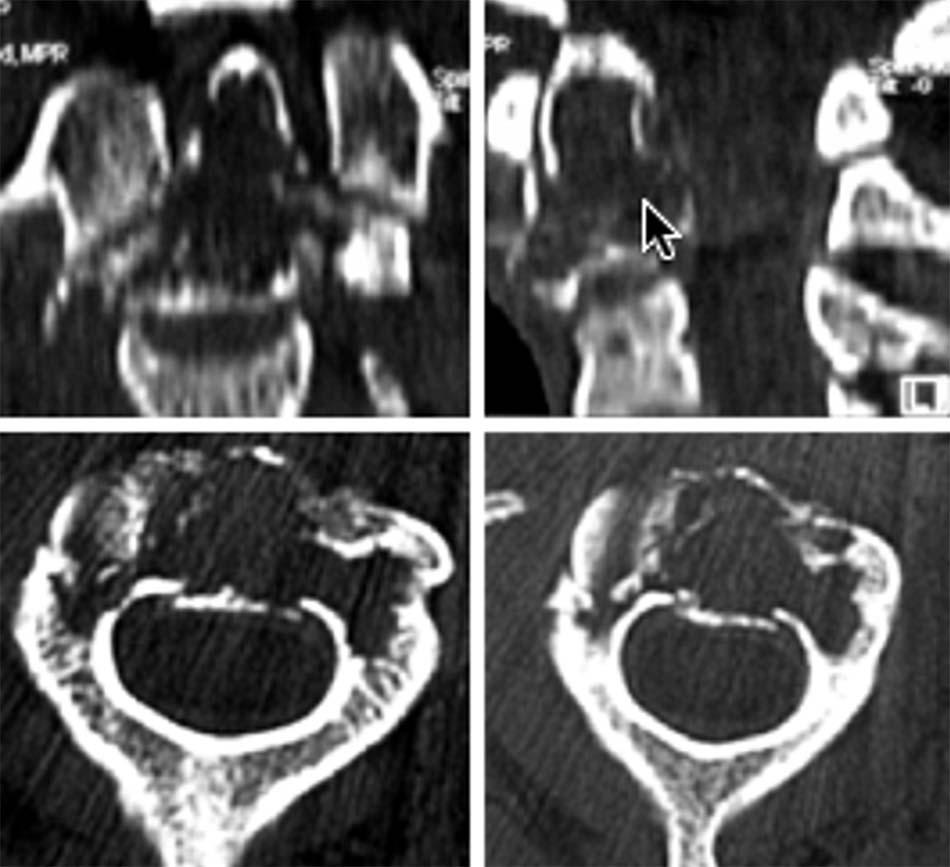

2.1.2. Vỡ đốt đội (C1)

Vỡ C1 gặp 1-2% trong các tổn thương gãy cột sống và chiếm tỷ lệ khoảng 15% gãy cột sống cổ. Năm 1822, Cooper lần đầu tiên mô tả gãy C1 sau khi mổ tử thi. Đến năm 1920, Jefferson mô tả tổn thương vỡ C1 , là loại gãy ít gây thương tổn thần kinh do làm rộng ống tủy. Theo Sonntag và cộng sự [50], thương tổn này chiếm 3-13% trong chấn thương cột sống cổ. Theo một thông báo tổng kết từ năm 1822 đến năm 1938 có 99 thông báo đề cập đến tổn thương này [7],[48],[42].

Đây là loại thương tổn gây ra do lực nén theo trục ngang giữa lồi cầu chẩm và C2 tạo ra gãy cung trước và sau và mảnh vỡ di lệch sang bên. Thông thường di lệch sang hai bên, đôi khi di lệch một bên nếu đầu bị xoay khi bị sang chấn. Thường bệnh nhân không có tổn thương thần kinh [11] [22].

Vị trí thương tổn thường ở 4 điểm yếu ở cung trước và cung sau, nơi tiếp giáp với 2 khối bên. Có nhiều cách phân loại thương tổn, Levine và Edwards [20] phân thành 3 loại thương tổn theo vị trí và số điểm gãy trên cung trước, cung sau:

- Loại I: vỡ cung sau C1 đơn thuần, tổn thương thường gặp nhất, gãy vững, không tổn thương dây chằng ngang.

Hình 1.24. Hình ảnh vỡ cung sau C1 đơn thuần (loại 1) - Loại II: gãy kết hợp một cung trước và một cung sau do lực ép thẳng trục phối hợp với nghiêng đầu. Thương tổn ít gặp nhất của vỡ C1. Hậu quả làm bửa một khối bên C1.

Hình 1.25. Hình ảnh vỡ cung sau C1 (loại 2) - Loại III: vỡ vụn C1 (gãy Jefferson). Tổn thương thường gặp sau gãy loại I, cơ chế do lực nén thẳng trục với tư thế đầu trung gian, tổn thương gãy 2 điểm cung trước và 1 hoặc 2 điểm ở cung sau.

Hình 1.26. Hình ảnh vỡ vụn C1 – gãy Jefferson (loại 3)

Từ khi có chụp cắt lớp và cộng hưởng từ, người ta có thể phát hiện các thương tổn dây chằng ngang phối hợp với vỡ C1, vì vậy hầu hết đều thống nhất chia làm 2 loại:

- Vỡ C1 đơn thuần: thương tổn vững, điều trị bảo tồn.

- Vỡ C1 kèm rách dây chằng ngang: vỡ cung sau và cung trước C1 có thể làm căng rộng sang bên của hai khối bên gây rách dây chằng ngang. Spence và cộng sự [41] nghiên cứu trên tử thi thấy khi khối bên căng rộng quá 6,9 mm sẽ gây rách hoàn toàn dây chằng ngang. Đây là thương tổn mất vững và dễ di lệch thứ phát [48].

Khi chỉ số Spence > 6,9 chẩn đoán xác định đứt dây chằng ngang, tổn thương mất vững [11] [30] [42].